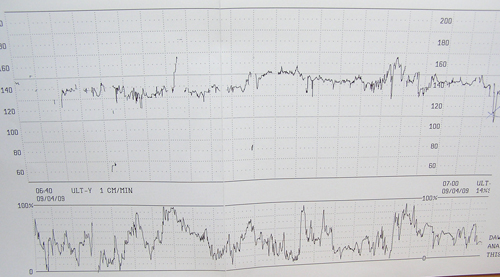

CTG:minden oké,Iza úgy rugdosott!Úgy néz ki sikerült túlpörgetni(csoki,szőlőcukor,kakaó).Így is 23 percig feküdni...már minden bajom volt.Főleg h olyan meleg volt odabenn!!Most fájást abszolút nem mutatott,viszont van ráírva vmi:tocorossz.Mond ez vkinek vmit?Most ez toco rossz?A toco az mi?